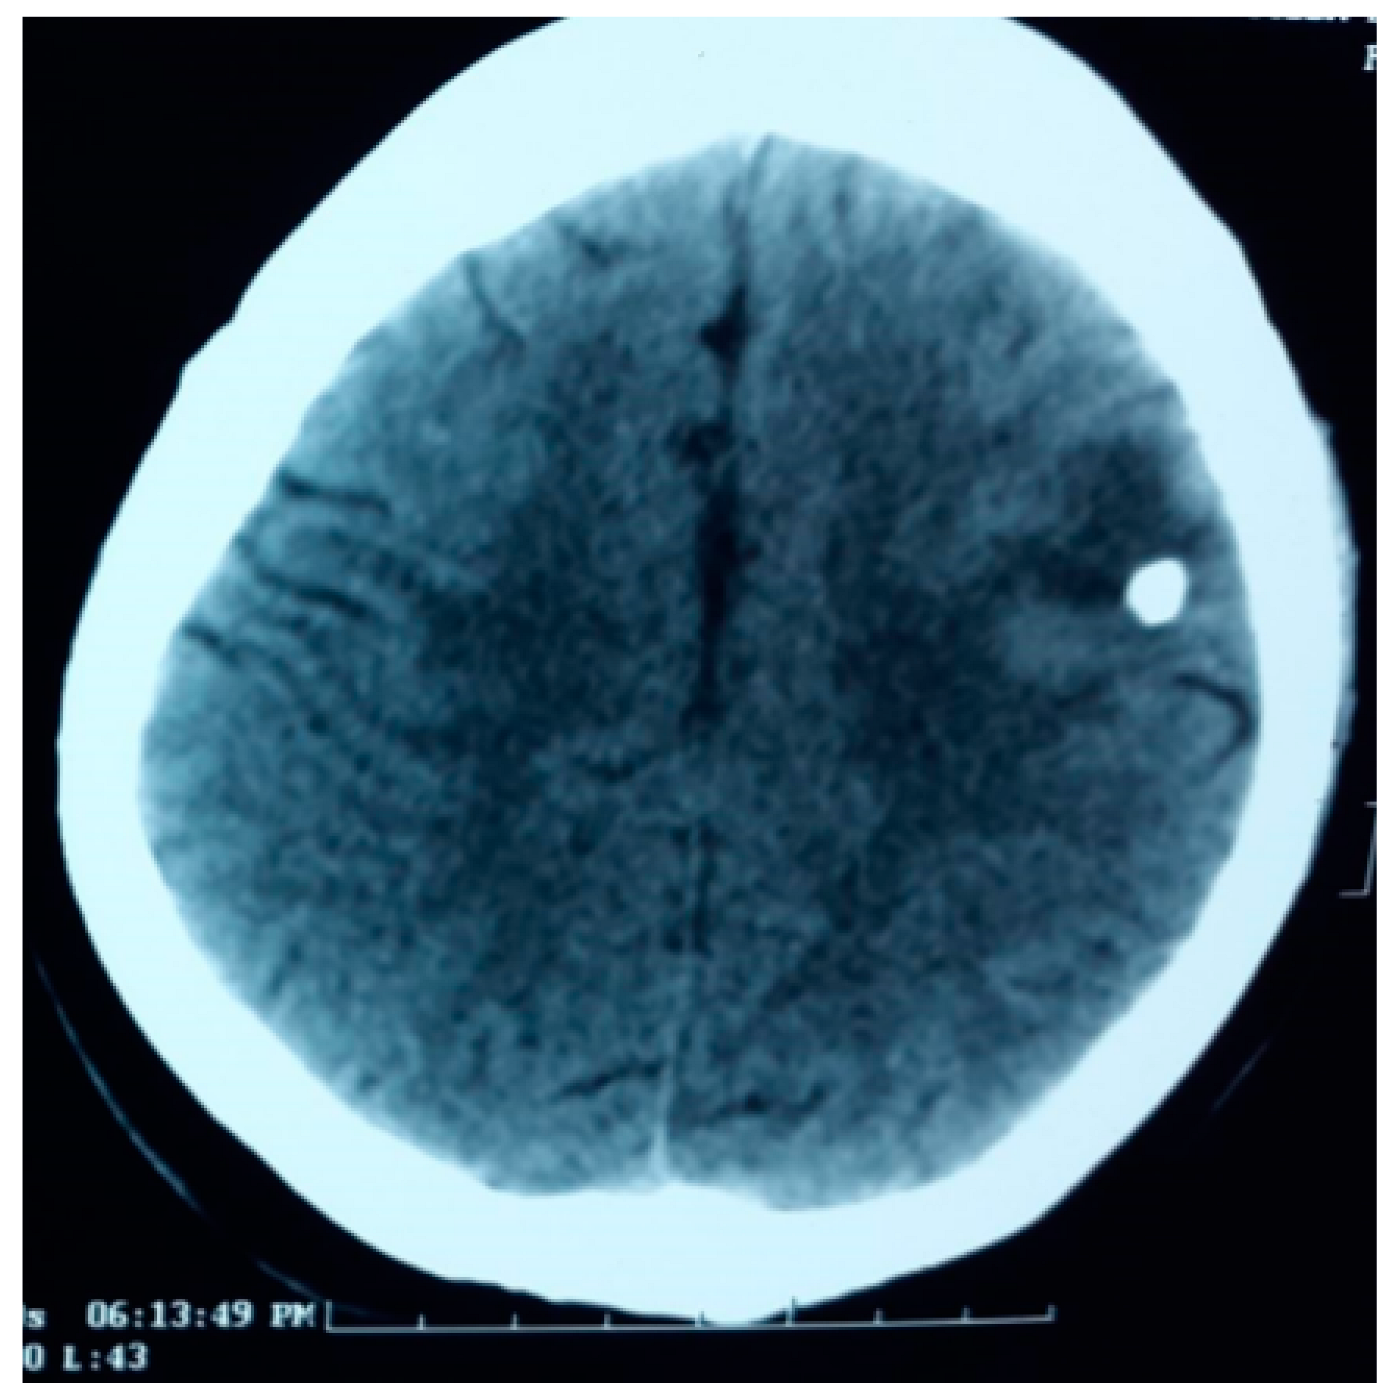

4. SCG: Risk Factors for Calcification

- Mahajan, L.; Malhotra, H.S.; Rizvi, I.; Kumar, N.; Garg, R.K.; Verma, R.; Sharma, P.K. Predictors of Lesion Calcification in Patients with Solitary Cysticercus Granuloma and New-Onset Seizures. Am. J. Trop. Med. Hyg. 2016, 95, 623–628. [Google Scholar] [CrossRef]

- Bustos, J.A.; Arooya, G.; Gilman, R.H.; Soto-Becerra, P.; Gonzales, I.; Saavera, H.; Pretell, E.J.; Nash, N.T.; O’Neal, S.E.; Del Brutto, O.H.; et al. Frequency and determinant factors for calcification neurocsyticercosis. Clin. Infect. Dis. 2021, 73, e2592–e2600. [Google Scholar] [CrossRef]